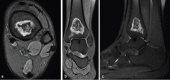

Figure 3

Axial (a), coronal (b), and sagittal (c) views of the left ankle magnetic resonance imaging Fat-Sat T2 sequence showing osteonecrosis of the distal tibia.

Figure 4

Axial (a–c) and sagittal (d–f) views of the right ankle, magnetic resonance imaging Fat-Sat T2 sequence showing smaller areas of osteonecrosis of the distal tibia.